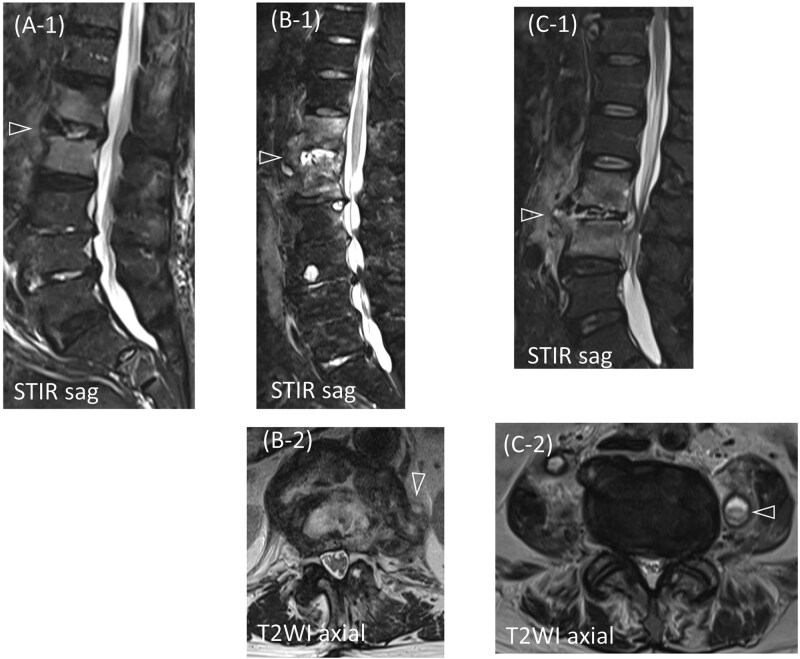

化脓性脊柱炎和弥漫性特发性骨骼肥厚症(DISH)都可以发生在老年人的胸腰椎。在化脓性脊柱炎患者中,据报道,DISH患者的死亡率明显高于非DISH患者。然而,死亡率增加的原因和预防致命后果的有效战略仍有待确定。在这里,我们报告三例化脓性脊柱炎影响非强直性病变的老年DISH患者。这些患者成功地使用穿透性终板螺钉进行前后固定,提供牢固的固定,在DISH中特别有利。对于伴有非强直性病变的化脓性脊柱炎患者,在计算机断层扫描和磁共振成像的指导下,采用穿透性终板螺钉进行早期脊柱固定,可能有助于防止老年患者卧床不起。

Both pyogenic spondylitis and diffuse idiopathic skeletal hyperostosis (DISH) can develop in the thoracolumbar spine of older adults. Among patients with pyogenic spondylitis, those with DISH reportedly have a significantly higher mortality rate than those without DISH. However, the reasons for this increased mortality and effective strategies for preventing fatal outcomes remain to be determined. Here, we report three cases of pyogenic spondylitis affecting non-ankylotic lesions in older patients with DISH. These patients were successfully treated with anterior and posterior fixation using penetrating endplate screws, which provide strong fixation and are particularly advantageous in DISH. In cases of pyogenic spondylitis involving non-ankylotic lesions in DISH, early spinal fixation with penetrating endplate screws, guided using computed tomography and magnetic resonance imaging, may help prevent older adult patients from becoming bedridden.